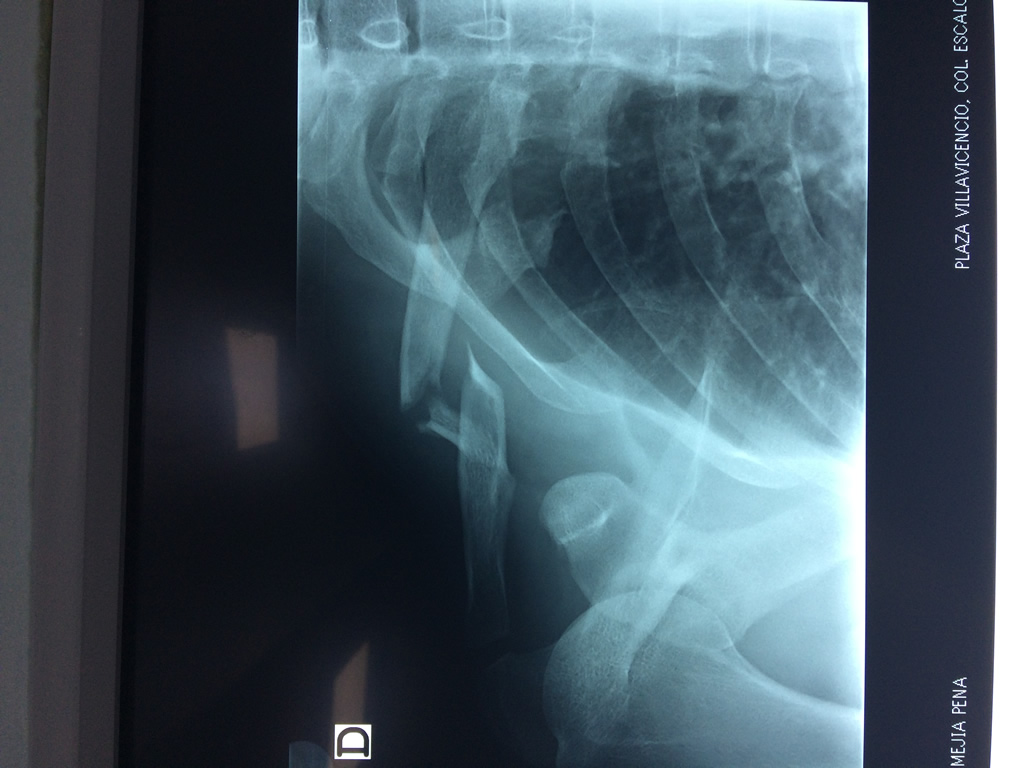

Clavicula 4

Detail Download